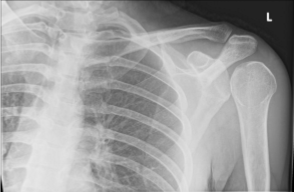

shoulder - anterior dislocation

shoulder - posterior dislocation